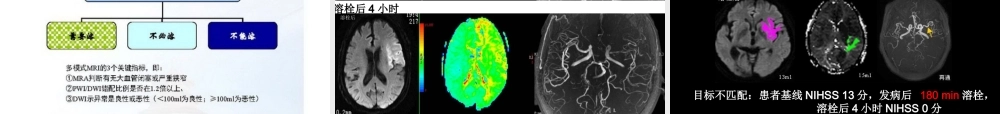

急性缺血性脑卒中的规范化诊治中南大学湘雅医院神经内科刘运海2014-09-27迅速评估和诊断一特异性治疗二三急性缺血性脑卒中的规范化诊治四一般处理急性期并发症的处理第一部分迅速评估和诊断脑卒中的评估和诊断包括:1.病史和体征2.影像学检查3.实验室检查4.疾病诊断5.病因分型6.诊断流程急诊室绿色通道病史和体征1.病史采集:询问症状出现的时间最为重要。其他包括神经症状发生及进展特征,心脑血管病危险因素,用药史、药物滥用、偏头痛、痫性发作、感染、创伤及妊娠史等。2.评估气道、呼吸和循环功能后,立即进行一般体格检查和神经系统体检。3.可用美国国立卫生院脑卒中量表(NIHSS)评估病情严重程度。影像学检查脑病变检查1.NNCT2.多模式CT3.标准MRI4.多模式MRI(DWI、PWl、GRE)血管病变检查1.颈动脉双功超声2.TCD3.MRA4.CTA5.DSA实验室检查必做检查1.NNCT或MRI2.血糖、肝肾功能和电解质3.心电图和心肌缺血标志物4.血常规5.凝血机制(PT、INR、APTT)6.氧饱和度7.胸片可选检查1.毒理学筛查2.血液酒精水平3.妊娠试验4.动脉血气分析5.腰穿(SAH?感染?)6.脑电图(癫痫发作?)疾病诊断1.急性起病2.局灶性神经功能缺损,少数为全面神经功能缺损3.症状和体征持续24h以上(溶栓可参照适应证选择患者)4.排除非血管性脑部病变5.脑CT或MRI排除脑出血和其他病变,有责任缺血病灶。病因分型-CISS分型诊断流程1.是否为脑卒中?排除非血管性疾病。2.是否为缺血性脑卒中?进行脑CT或MRI检查排除出血性脑卒中。3.脑卒中严重程度?根据神经功能缺损量表评估。4.能否进行溶栓治疗?核对适应证和禁忌证。5.病因分型?参考TOAST及CISS分型,结合病史、实验室、脑病变和血管病变等检查资料确定病因。推荐意见1.在溶栓等治疗前,所有脑卒中患者应进行头颅NNCT、心电图、血液学、凝血功能和生化检查(I级推荐)。2.用神经功能缺损量表评估病情程度(Ⅱ级推荐)。3.应进行血管病变检查(II级推荐),但在症状出现6h内,不过分强调此类检查。4.根据上述规范的诊断流程进行诊断(I级推荐)。脑卒中单元•脑卒中单元是组织化管理住院脑卒中患者的医疗模式,把传统治疗脑卒中的各种独立方法,如药物治疗、肢体康复、语言训练、心理康复、健康教育等组合成一种综合的治疗系统。脑卒中单元明显降低了脑卒中患者的病死率和残疾率。•推荐意见:收治脑卒中的医院应尽可能建立脑卒中单元,所有急性缺血性脑卒中患者应尽早、尽可能收入脑卒中单元(I级推荐,A级证据)或...